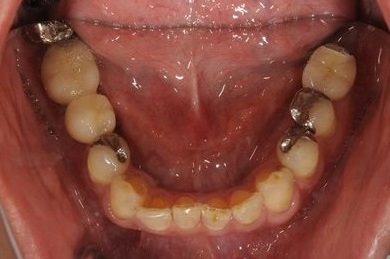

抜歯即日スピードインプラント治療

| 性別/年齢 | 男性 / 36歳 | ||||||||||||||||||||||||||||||||

| 主訴 | 義歯・インプラントの相談。 | ||||||||||||||||||||||||||||||||

| 治療方針 | 抜歯と同時にインプラント埋入を行い、治療期間を短縮する。 | ||||||||||||||||||||||||||||||||

| 治療内容 | インプラント4本(抜歯即日スピードインプラント)、メタルボンドセラミッククラウン4本 | ||||||||||||||||||||||||||||||||

| 総治療費 | 1,457,888円 | ||||||||||||||||||||||||||||||||

| 治療期間 | 1年7ヶ月 |